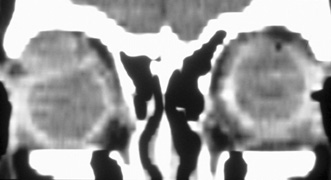

Valuable information about the nature and extent of an orbital pathologic process is provided by imaging studies such as computed tomography (CT) scan, magnetic resonance imaging (MRI), and orbital echography. Better spatial resolution, ready accessibility, and lower cost make CT the preferred choice for orbital imaging in most cases. Orbital fat provides a natural contrast between most adjacent orbital structures on CT scanning, and orbital bones are visualized well. Computed tomography is essential for evaluation of the orbital bones because they cannot be imaged with MRI. Direct coronal or sagittal images are important to identify the relationship of a lesion to the optic nerve so that the surgical approach can be planned to avoid traversing the optic nerve (Fig. 1).

Fig. 1. A. Axial CT scan demonstrating a large, well-encapsulated lesion in the orbital apex. Coronal (B) and sagittal (C) scans demonstrate that the mass lies inferior and medial to the optic nerve within the intraconal space. This information is useful in planning the surgical approach to the mass, which should avoid traversing the optic nerve.